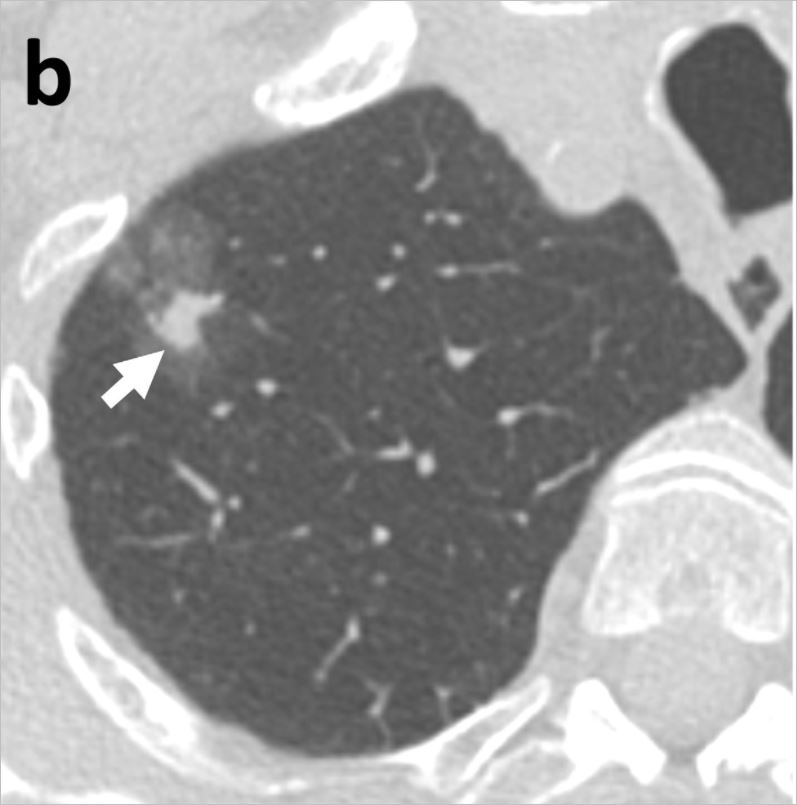

간유리 음영이란 CT로 폐를 촬영할 경우 영상에 뿌옇게 유리를 갈아 뿌려 놓은 것 같은 모양을 하고 있다면 붙여진 이름입니다. 아직까지 어떻게 치료해야 할지에 대해 명확한 기준이 나와 있지 않습니다. 최근 연구 결과에 의하면 간유리 음영의 대부분이 조직검사 결과 암이었다고 합니다.

연세대 강남세브란스병원 흉부외과 이성수, 문덕환 교수 연구팀은 2012년 5월부터 2016년 12월까지 강남세브란스병원에서 폐암이 의심돼 수술받은 환자 중 순수 간유리 음영으로 진단된 36명, 44례를 분석한 결과, 침윤성 선암이 10례(22.7%), 최소침윤성 선암이 15례(34.1%), 제자리암종 18례(40.9%), 비정형샘종증식이 1례(2.3%)로 나타났다고 24일 밝혔다. 제자리암종은 암세포가 기저막을 침윤하지 않고 상피층 내에만 있어 0기암이라고도 불리는데, 제자리암종까지 포함할 경우 간유리 음영 결절의 97% 이상이 암이었다는 뜻이다. 비정형샘종증식도 폐암이 되기 직전의 병변이기 때문에 사실상 분석한 간유리음영 모두 암으로 볼 수 있다고 연구팀은 설명했다.